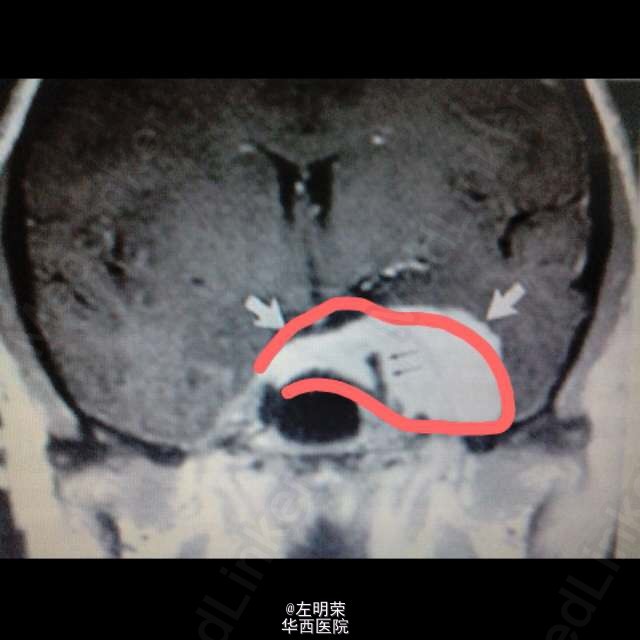

鞍旁区域脑膜瘤完全位于鞍内极少见,多起于鞍隔,女性多发,生长缓慢,可侵犯海绵窦,损害颅神经。下图冠状位MRI示:鞍旁区meningioma,且包绕了同侧颈内动脉。